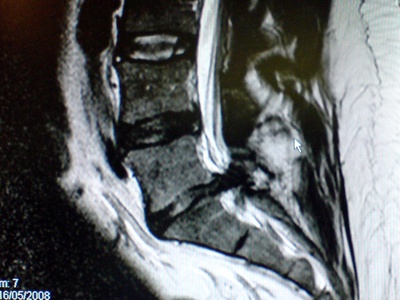

| Lumbar Discectomy | Neurosurgery/Spine | Decompress | Open or Minimally invasive |

Lumbar Discectomy

Removal of a herniated disc fragment pressing on spinal nerves to relieve leg pain (sciatica).

| Microdiscectomy | Neurosurgery/Spine | Decompress | Minimally invasive |

Microdiscectomy

Small, targeted removal of disc material pressing on a nerve to relieve leg pain while preserving surrounding structures.